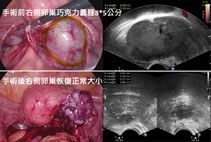

微創腹腔鏡卵巢巧克力囊腫切除術,圖片來源 (劉馨鎂醫師)

當藥物治療效果不佳時,手術是治療卵巢巧克力囊腫的常見選擇。雖然手術可去除囊腫並改善症狀,但可能影響卵巢功能,且子宮內膜異位症具有高復發率的特性,未來可能需再次手術。因此,手術後可搭配藥物治療,減少復發風險。

手術後,卵巢功能可能會下降,特別是如果曾做過多次手術,未來取卵的數量可能會變少。。因此,對於尚未生育的年輕女性或卵巢功能已偏低者,建議在手術前考慮先凍卵,以保留生育力。